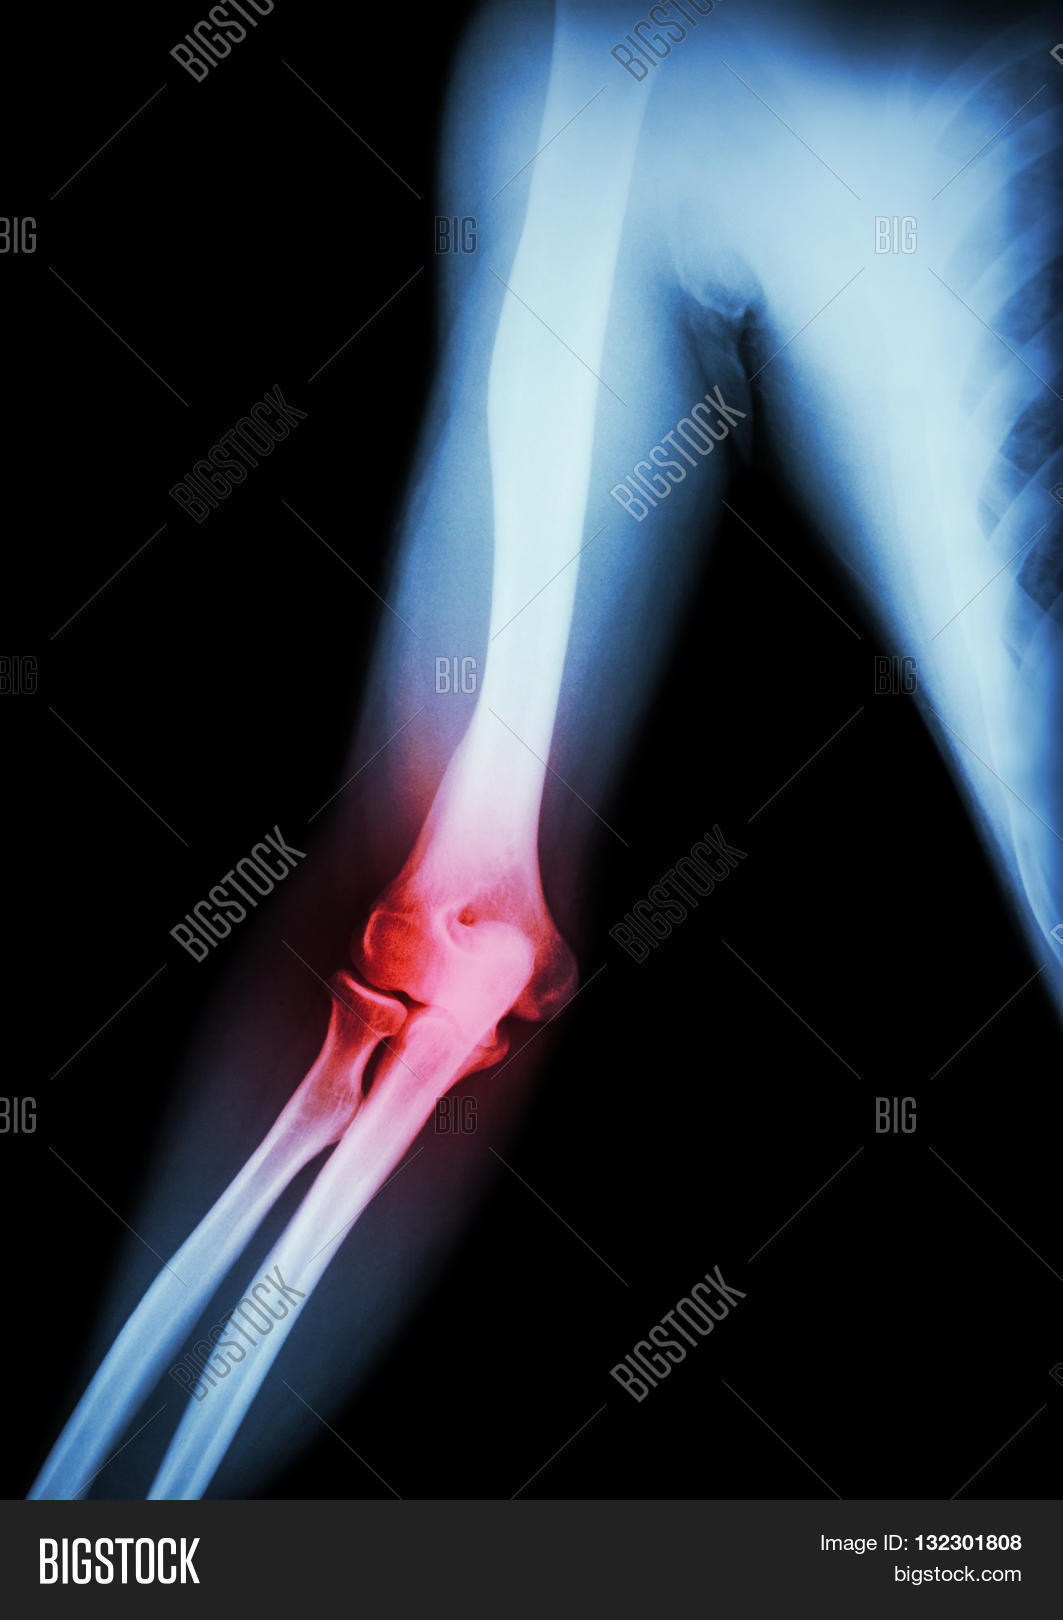

From www.bigstockphoto.com

Arthritis at elbow . film xray of arm elbow forearm and inflammation Arthritis In Elbow And Forearm Elbow osteoarthritis is a form of arthritis that causes pain, stiffness, and decreased motion of the elbow joint. Humerus, or upper arm bone. If you are experiencing pain, swelling and stiffness in the elbows, you may have one of the following types of arthritis or related conditions. Rheumatoid arthritis is an autoimmune disease that attacks the lining of the joints,. Arthritis In Elbow And Forearm.